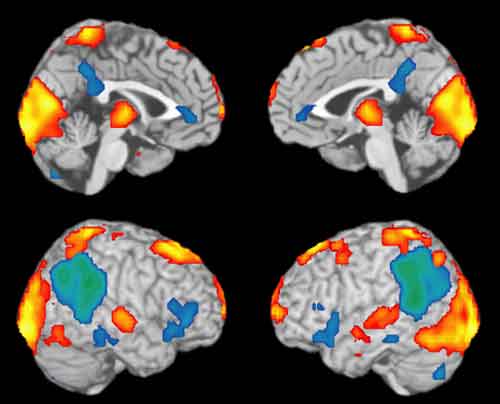

La ricerca di Krook-Magnuson e colleghi è stata condotta su topi geneticamente modificati in modo da ottenere diverse popolazioni di neuroni con opsine sensibili alla luce. I ricercatori hanno dimostrato che, una volta rilevati in tempo reale grazie a un encefalogramma combinato con un apposito programma, gli attacchi epilettici ai lobi frontali possono essere fermati mediante l’uso di un’opportuna radiazione luminosa. Le strategie d’intervento in realtà sono state due, antitetiche tra loro. In una infatti era prevista l’inibizione dei neuroni con funzione eccitatoria, viceversa nell’altra erano attivati neuroni dell’ippocampo con funzione inibitoria.

Questi risultati dimostrano che gli attacchi spontanei nel lobo temporale possono essere rilevati e arrestati modulando specifiche popolazioni di cellule. Secondo gli autori, i risultati mostrano il potenziale di questo tipo di approccio, che potrebbe consentire la definizione di protocolli d’intervento anche sull’essere umano per questo tipo di epilessia.